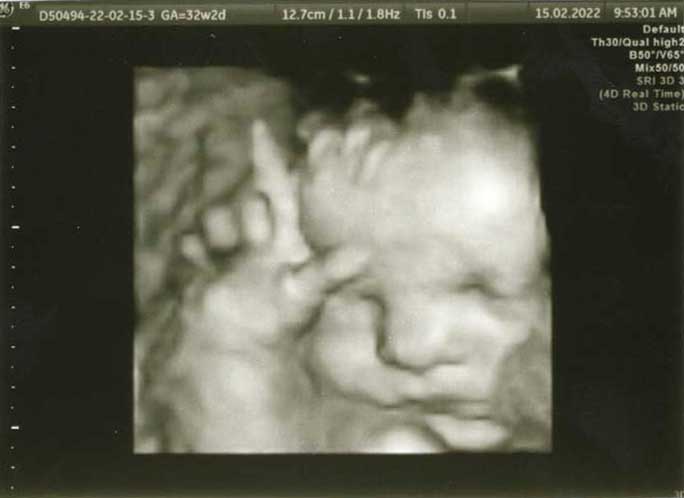

3D/4D HD LIVE

Στο ιατρείο μας προσφέρουμε υψηλής ευκρίνειας 3D και 4D τεχνολογία απεικόνισης του εμβρύου. Η τεχνολογία αυτή αποτελεί ένα ακόμα σημαντικό διαγνωστικό όπλο στη φαρέτρα του προγεννητικού ελέγχου, ενώ ταυτόχρονα ενισχύει την ανάπτυξη του δεσμού ανάμεσα στους μελλοντικούς γονείς και το μωρό τους.